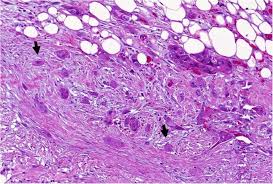

Learn Pancreatic Cancer Overview Craig S Cause Pancreatic Cancer Society from uploads-ssl.webflow.com Pancreatic cancer is notoriously difficult to diagnose. We'd also like to use analytics cookies. Inability to digest fatty foods, which can result in large, greasy stools. Pancreatic cancer symptoms and signs often do not manifest until the cancer has metastasized. The stage of cancer refers to how far it has on physical exam, the doctor may feel a mass in the center of the abdomen. Here, the common symptoms of pancreatic cancer. This is something you have to talk over with your. Pancreatic cancer is a disease caused by malignant, cancerous cells forming in the tissues of the pancreas.